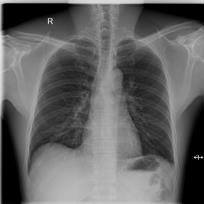

Chest X-ray (CXR) is the most typical radiological exam for diagnosis of various diseases. Due to the expensive and time-consuming annotations, detecting anomalies in CXRs in an unsupervised fashion is very promising. However, almost all of the existing methods consider anomaly detection as a One-Class Classification (OCC) problem. They model the distribution of only known normal images during training and identify the samples not conforming to normal profile as anomalies in the testing phase. A large number of unlabeled images containing anomalies are thus ignored in the training phase, although they are easy to obtain in clinical practice. In this paper, we propose a novel strategy, Dual-distribution Discrepancy for Anomaly Detection (DDAD), utilizing both known normal images and unlabeled images. The proposed method consists of two modules, denoted as A and B. During training, module A takes both known normal and unlabeled images as inputs, capturing anomalous features from unlabeled images in some way, while module B models the distribution of only known normal images. Subsequently, the inter-discrepancy between modules A and B, and intra-discrepancy inside module B are designed as anomaly scores to indicate anomalies. Experiments on three CXR datasets demonstrate that the proposed DDAD achieves consistent, significant gains and outperforms state-of-the-art methods. Code is available at https://github.com/caiyu6666/DDAD.